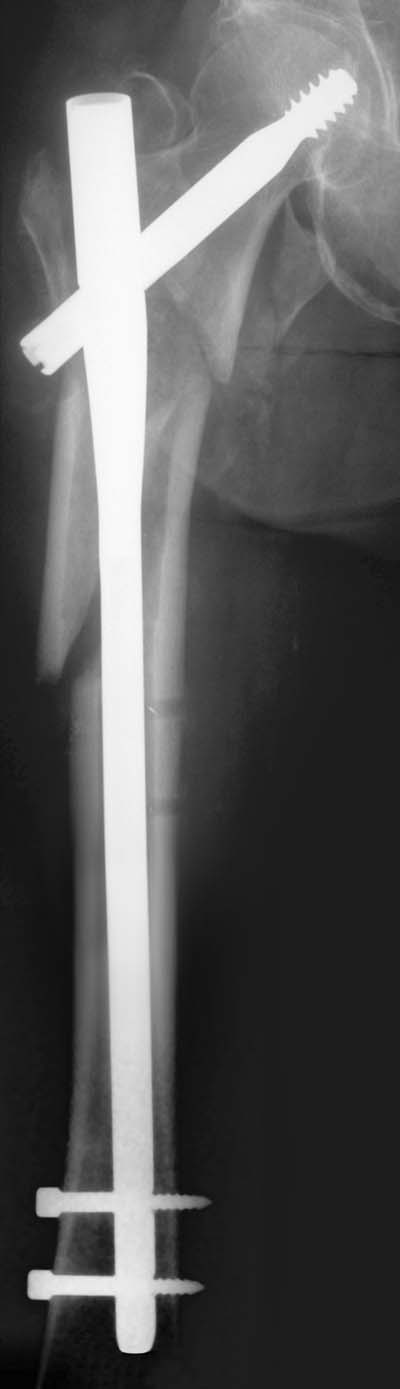

De Gamma-nagel zoals zij is bevestigd in het bovenbeen.

Foto